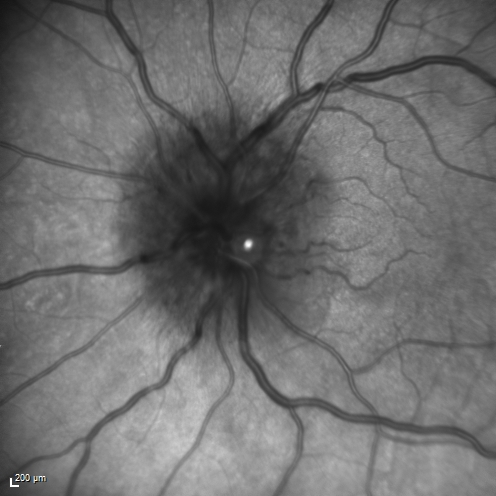

Syphillitic Optic Neuropathy and Maculopathy

46 year old woman with 2 weeks of vision loss OD.  VA 20/200 OD; 20/20 OS.  there are posterior vitreous cells on OCT in both eyes.  ICG, FAF, and FA show an abnormal macula OD.  VA improved to 20/30 within a month with treatment with PCN.